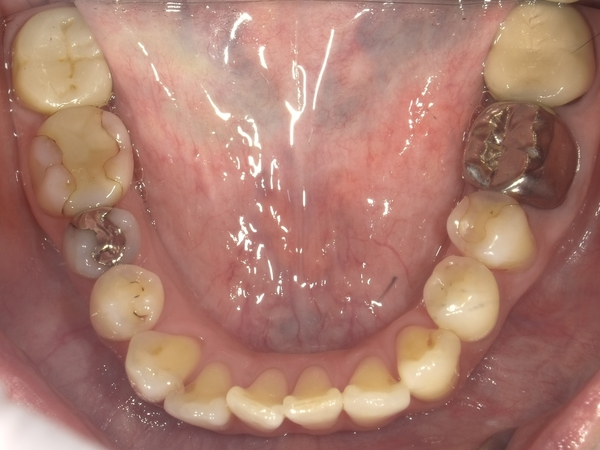

Before After

●ご相談内容:前歯が曲がっている●矯正の種類:マウスピース型「矯正インビザラインGO」●治療期間:18週●治療費用:66万円(税込)